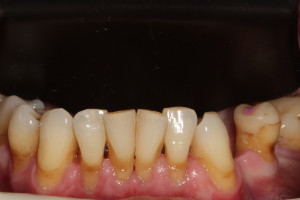

Pacjent lat 60, duże recesje dziąseł, niewyedukowany w zakresie prawidłowej higieny jamy ustnej. Został skierowany na higienizację profesjonalną przez lekarza prowadzącego. Na pierwszej wizycie siekacze dolne pacjenta wyglądały tak: zdjęcie 1, zdjęcie 4.

Widać wyraźnie, że kamień i gruba warstwa płytki bakteryjnej wywołał stan zapalny dziąseł – są przekrwione, i opuchnięte. Higienistka wykonała skaling naddziąsłowy skalerem EMS, wypiaskowała zęby piaskiem Air-Flow Plus oraz wypolerowała pasta polerską. Po zabiegu różnica wyglądzie zębów jest diametralna: zdjęcie 2, zdjęcie 5.

Naszym celem jednak jest nie tylko ładny wygląd zębów ale wyleczenie stanu zapalnego dziąseł, a to nie będzie możliwe bez dokładnego wyedukowania pacjenta. Higienistka przeprowadziła szczegółowy instruktarz prawidłowej metody szczotkowania – pokaz na modelu i samodzielna próba pacjenta na własnych zębach. Pacjent nauczył się również stosowania szczoteczek międzyzębowych, będących w jego przypadku niezbędnym akcesorium higienicznym ze wglądu na szerokie przestrzenie miedzyzębowe. Zalecone zostały środki pomocnicze – Eludril do płukania, pasta Elgydium Anti-Pacjent spotkał się z nasza higienistka jeszcze dwa razy, w celu dokonania kontroli i ewentualnego doczyszczenia. Na drugiej wizycie kontrolnej dziąsła pacjenta wyglądały tak: zdjęcie 3, zdjęcie 6. Komentarz jest chyba zbędny: różnica widoczna gołym okiem, dziąsła są zdrowe, bladoróżowe, bez opuchlizny. Gratulujemy!!!